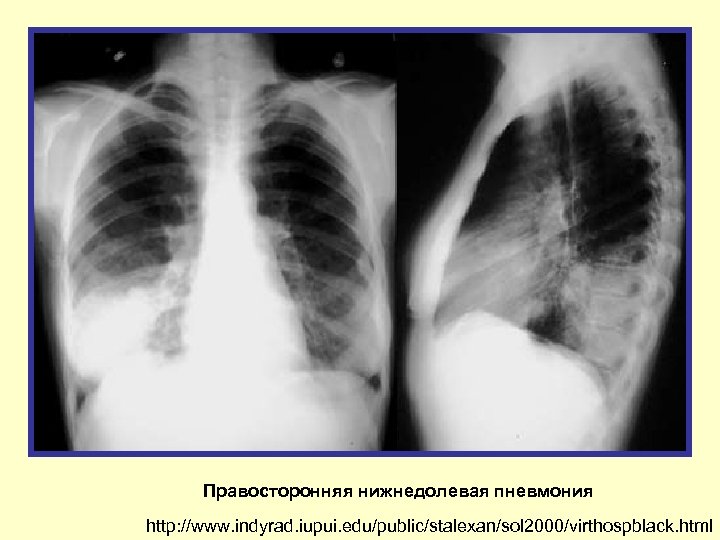

Правосторонняя нижнедолевая пневмония http: //www. indyrad. iupui. edu/public/stalexan/sol 2000/virthospblack. html